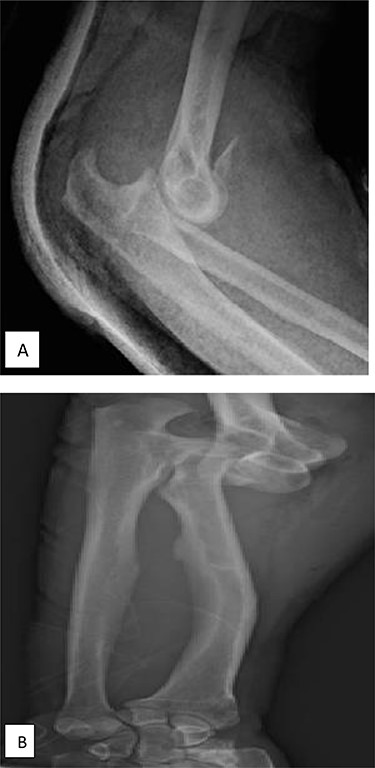

A 56-year-old male fell forward onto his forearm and elbow during a mountain walk. He reported immediate swelling and pain in his elbow and wrist. On examination, there was a deformity of his right elbow with pain in the ipsilateral wrist; there were no skin or distal neurovascular disorders. Initial lateral radiographs requested by the emergency doctor focused on the elbow and showed a posterior dislocation of the right elbow with a type II Mason radial head fracture with a small detached fragment <20%, associated to a proximal radioulnar joint (PRUJ) dislocation and a coronoid fracture type 2 according to the O’Driscoll classification with an anterior avulsion of an anteromedial coronoid small fragment (Fig. 1A). There was mild widening of the DRUJ with significant ulnar negative variance (Fig. 1B).

(A) X-ray of elbow profile shows the posterior elbow dislocation with a detached anterior fragment from the coronoid; (B) three-fourth X-ray of the forearm before the reduction demonstrates significant ulnar negative variance.